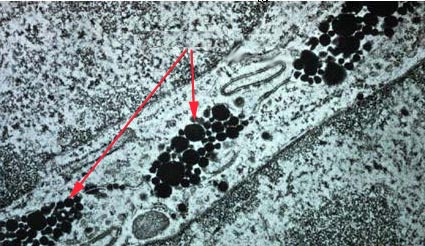

Identify structures indicated by the arrows in the lateral aspect of intestinal absorptive cells.

Chylomicrons